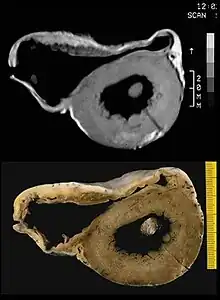

There are two pathological patterns seen in ACM, Fatty infiltration and fibro-fatty infiltration.

Fatty infiltration

The first, fatty infiltration, is confined to the right ventricle. This involves a partial or near-complete substitution of myocardium with fatty tissue without wall thinning. It involves predominantly the apical and infundibular regions of the RV. The left ventricle and ventricular septum are usually spared. No inflammatory infiltrates are seen in fatty infiltration. There is evidence of myocyte (myocardial cell) degeneration and death seen in 50% of cases of fatty infiltration.

Fibro-fatty infiltration

The second, fibro-fatty infiltration, involves replacement of myocytes with fibrofatty tissue. A patchy myocarditis is involved in up to 2/3 of cases, with inflammatory infiltrates (mostly T cells) seen on microscopy. Myocardial atrophy is due to injury and apoptosis. This leads to thinning of the RV free wall (to < 3 mm thickness) Myocytes are replaced with fibrofatty tissue. The regions preferentially involved include the RV inflow tract, the RV outflow tract, and the RV apex. However, the LV free wall may be involved in some cases. Involvement of the ventricular septum is rare. The areas involved are prone to aneurysm formation.

A post mortem histological demonstration of full thickness substitution of the RV myocardium by fatty or fibro-fatty tissue is consistent with ACM.